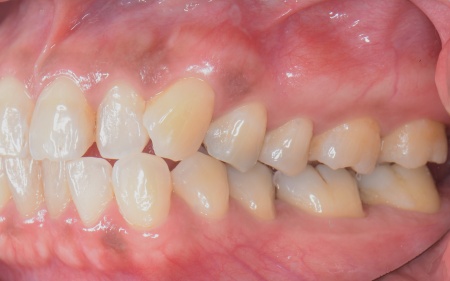

続いて噛み合わせを拝見したところ、前歯がしっかりと噛み合わない開咬(かいこう)という状態です。

この開咬により、本来前歯で分散して受け止めるべき噛む力が、すべて奥歯に集中していることがわかりました。そのため下顎隆起が発生し、また重度歯周病の大きな原因になっていると考えられます。

矯正方法としては、上下の歯全体の表面にブラケットと呼ばれるボタン状の装置を接着し、そこにワイヤーを通して歯を動かすマルチブラケット装置を採用しました。

とくに上の左右奥歯には、矯正用ミニインプラント(矯正治療専用の小さなネジ)を埋入し、奥歯を歯茎の方向に押し下げる「圧下」という治療を行っています。これにより開咬が解消され、前歯でしっかり噛めるようになりました。